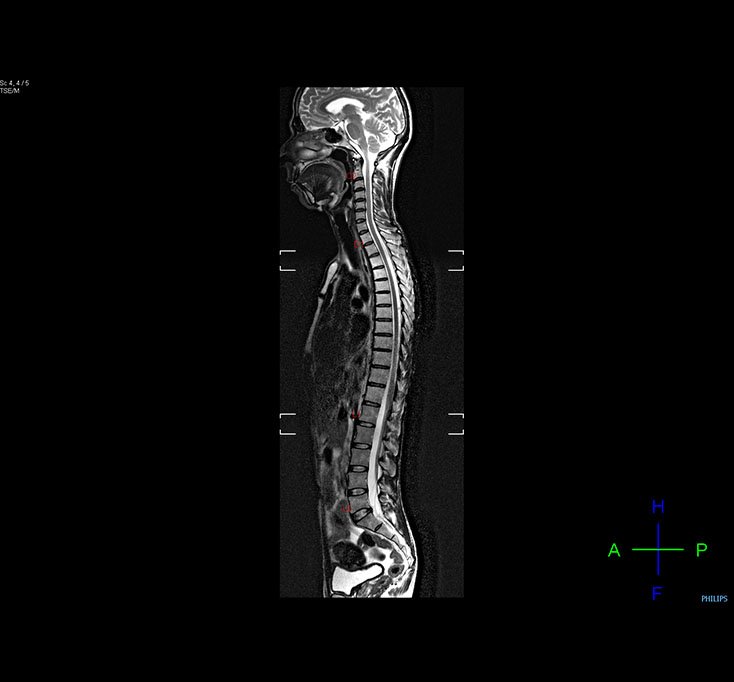

whole Body MRI

Whole Spine